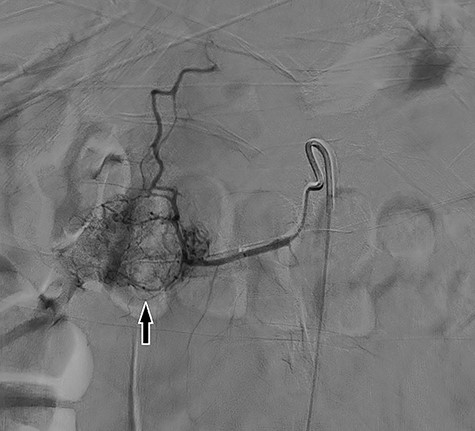

Digital subtraction angiography demonstrating large inferior pancreaticoduodenal arcade with superior reconstitution of the gastroduodenal artery and common hepatic artery and represents region of mass in without active contrast extravasation.

Our patient is a 30-year-old female with a past medical history of von Willebrand’s disease, bipolar disorder, major depressive disorder, anxiety and opioid abuse who presented to our hospital for right-sided abdominal pain and blood per rectum. She experienced massive hematemesis in the emergency department with blood pressure 98/55 mmHg, heart rate 145 bpm and respiratory rate 18 breaths per minute. Hemoglobin and hematocrit levels were 3.2 g/dl and 9.5%, respectively, and lactate level was 7.0 mmol/l. She promptly received 4 units of packed red blood cells with improvement of vital signs. Initial computed tomography (CT) of the abdomen and pelvis was negative for intra-abdominal pathology. Therefore, she was taken for emergent endoscopy. Esophagogastroduodenoscopy revealed an ulcerative mass of the second portion of the duodenum with overall poor visualization secondary to bleeding; biopsies were taken. Concomitant flexible sigmoidoscopy revealed blood in the rectum with no other pathologic findings. Emergency CT angiogram was performed revealing active hemorrhage into the duodenum (Fig. 1). The patient was admitted to the surgical intensive care unit where she underwent placement of resuscitative lines. Hemoglobin and hematocrit levels were 3.9 g/dl and 10.1% despite initial resuscitation and the patient was further transfused 6 units packed red blood cells, 2 pools of cryoprecipitate, 4 pools of platelets and 5 units of plasma; 1 g of tranexamic acid was given every 8 hours for 2 days. Per hematology recommendations, von Willebran factor/factor VIII complex (Humate-P) and desmopressin (1-deamino-8-D-arginine vasopressin, DDAVP) were administered. The patient underwent emergent mesenteric angiography by interventional radiology that revealed extensive vascular arcades at the second portion of the duodenum from the inferior pancreaticoduodenal artery without active extravasation (Fig. 2). The patient’s inappropriate response to multiple blood products necessitated emergent surgical exploration. Midline laparotomy revealed no gross hemoperitoneum. The hepatic flexure was mobilized and a Kocher maneuver was performed, revealing an ulcerative duodenal mass at the second portion of the duodenum. A longitudinal duodenotomy allowed for localization of an actively hemorrhaging mass 5 mm distal to the hepatopancreatic ampulla. The ampulla was cannulated with a pediatric feeding tube to mark its location during tumor resection. A wedge resection of the hemorrhagic duodenal mass was performed, including a small portion of nearby pancreatic head parenchyma. Hemostasis and preservation of bile flow through the ampulla was confirmed. The duodenotomy was hand-sewn in two layers transversely. A surgical drain was placed at the site of duodenal resection. The patient remained hypotensive and hypothermic, leading to a decision to institute damage control measures with temporary abdominal closure using a negative pressure wound therapy device. After further resuscitation and stabilization, the patient was brought back to the operating room 2 days later for planned re-exploration and definitive abdominal wall closure. Her postoperative recovery was complicated by a superficial incisional surgical-site infection that was treated successfully with drainage and a negative pressure wound therapy device, and she was discharged on hospital Day 22. Final surgical pathology revealed duodenal GIST measuring 2.5 × 2.0 × 1.4 cm with negative margins and no lymph nodes, corresponding to a pT2 tumor per the American Joint Committee on Cancer grading system. The GIST was mixed spindle and epitheliod type, CD117, CD34 and DOG 1 positive and CK7, AE1/AE3, synaptophysin and actin negative. The tumor had low mitotic rate, histologic Grade 1 with a Ki-67 index <5% and deemed low risk for recurrence. Due to the clinical and immunohistologic findings, observation without tyrosine kinase inhibitor therapy was the chosen management strategy. One-month follow-up was unremarkable and without symptoms of ongoing bleeding or recurrence.